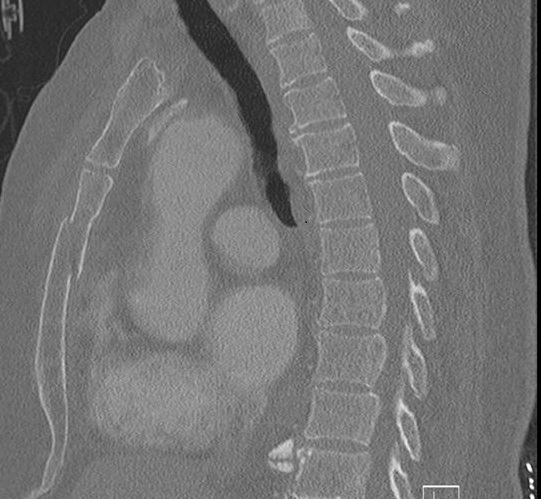

Image radiologique TDM en

coupe sagitale d'une fracture 1/3 moyen du sternum

avec aspect fracture de displacement glissante

antero-posterieure du sternum . |